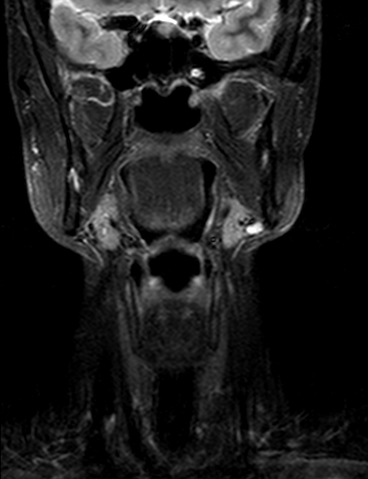

Prueba diagnóstica no invasiva que consiste en la obtención de imágenes de alta definición anatómica del cuello mediante el empleo de un campo electromagnético y ondas de radio (con un emisor y un receptor). No utiliza radiación ionizante. Indicaciones: sospecha de tumor, infecciones, ganglios.